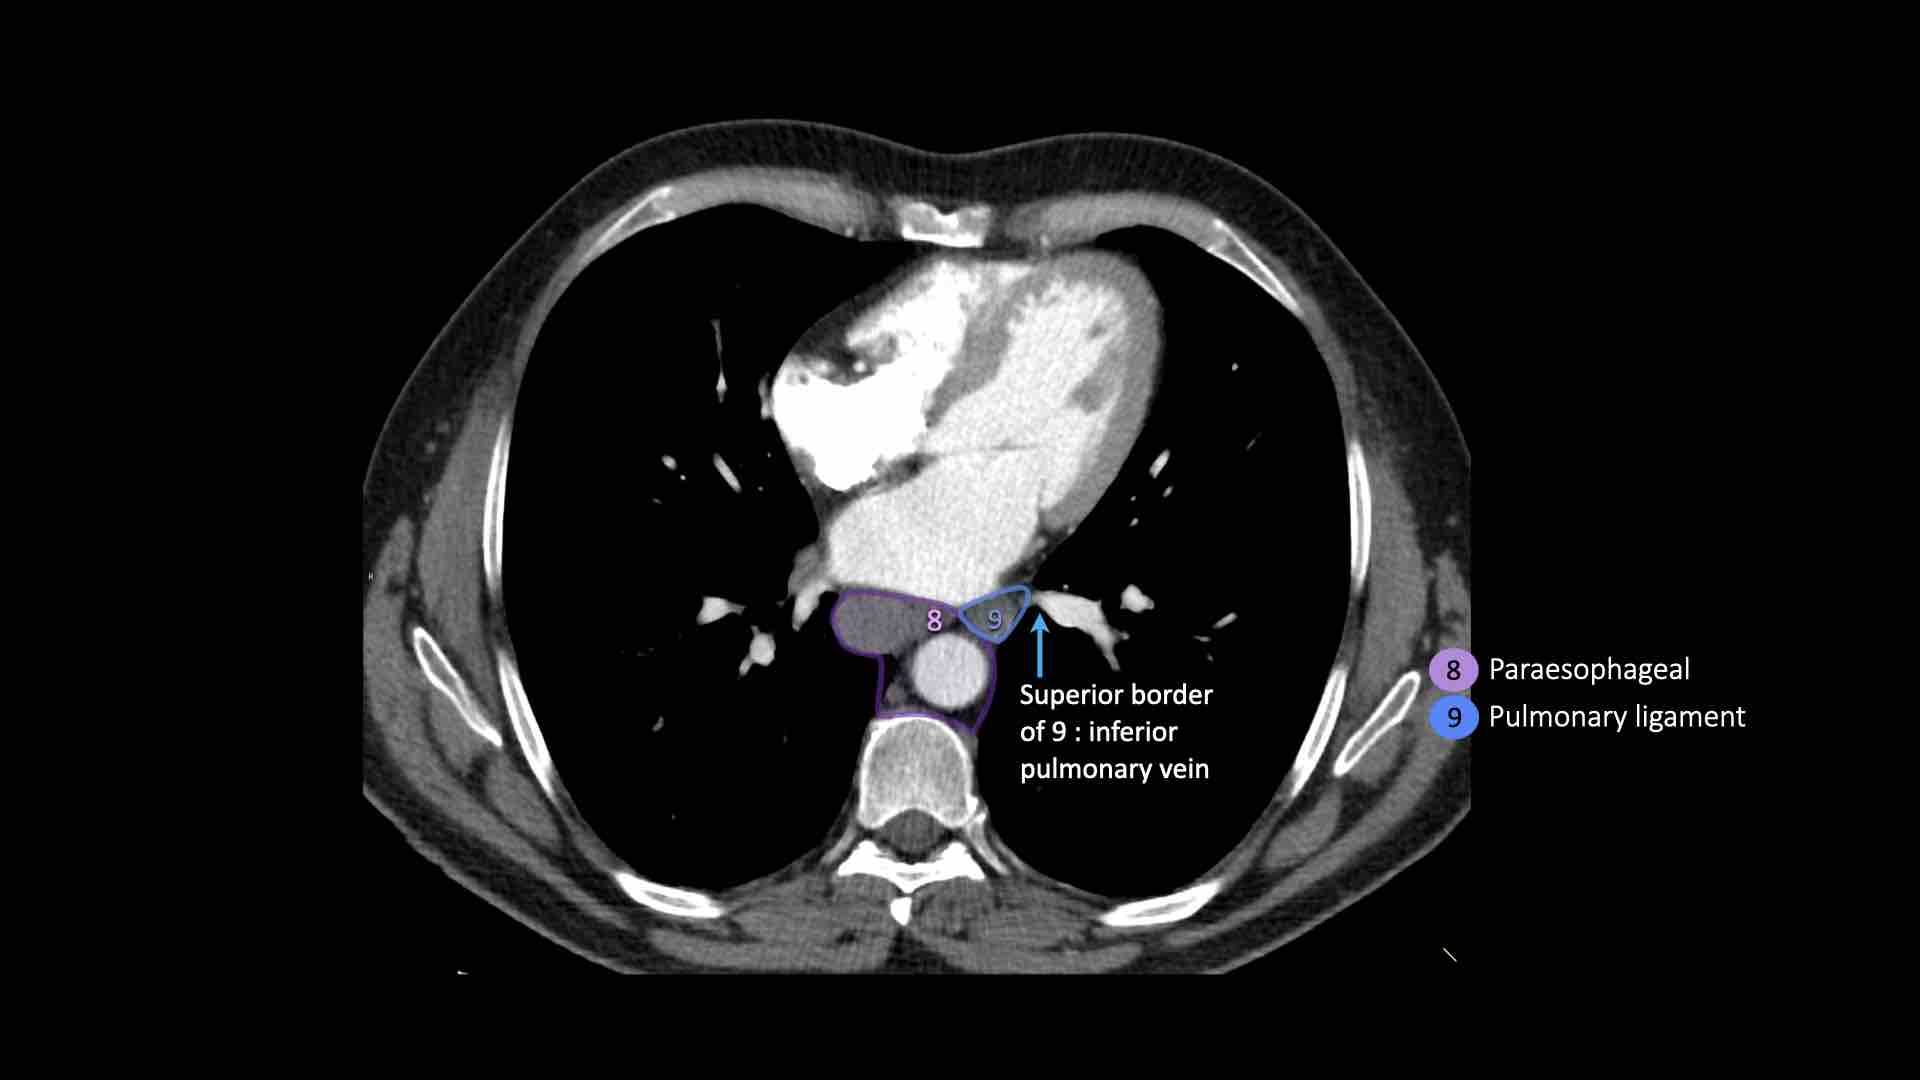

9. Dây chằng phổi

Các hạch nằm trong dây chằng phổi.

9. Hạch dây chằng phổi

Hạch dây chằng phổi nằm trong dây chằng phổi, bao gồm các hạch ở thành sau và phần dưới của tĩnh mạch phổi dưới.

Dây chằng phổi là phần kéo dài xuống dưới của các nếp gấp màng phổi trung thất bao quanh rốn phổi.

EUS đặc biệt hữu ích trong việc tiếp cận các hạch ở trung thất dưới (nhóm 7, 8 và 9).